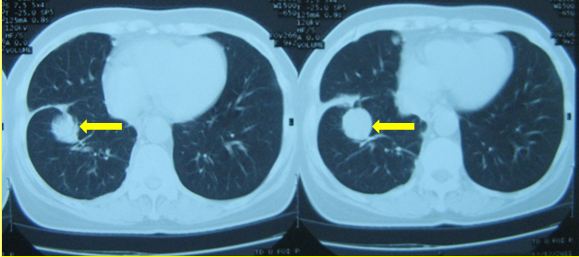

CT lồng ngực (12/12/011)

Hình 3: Hình ảnh chụp CT lồng ngực - u thùy dưới phổi phải: 28× 25mm, kèm theo nốt mờ nhỏ xung quanh